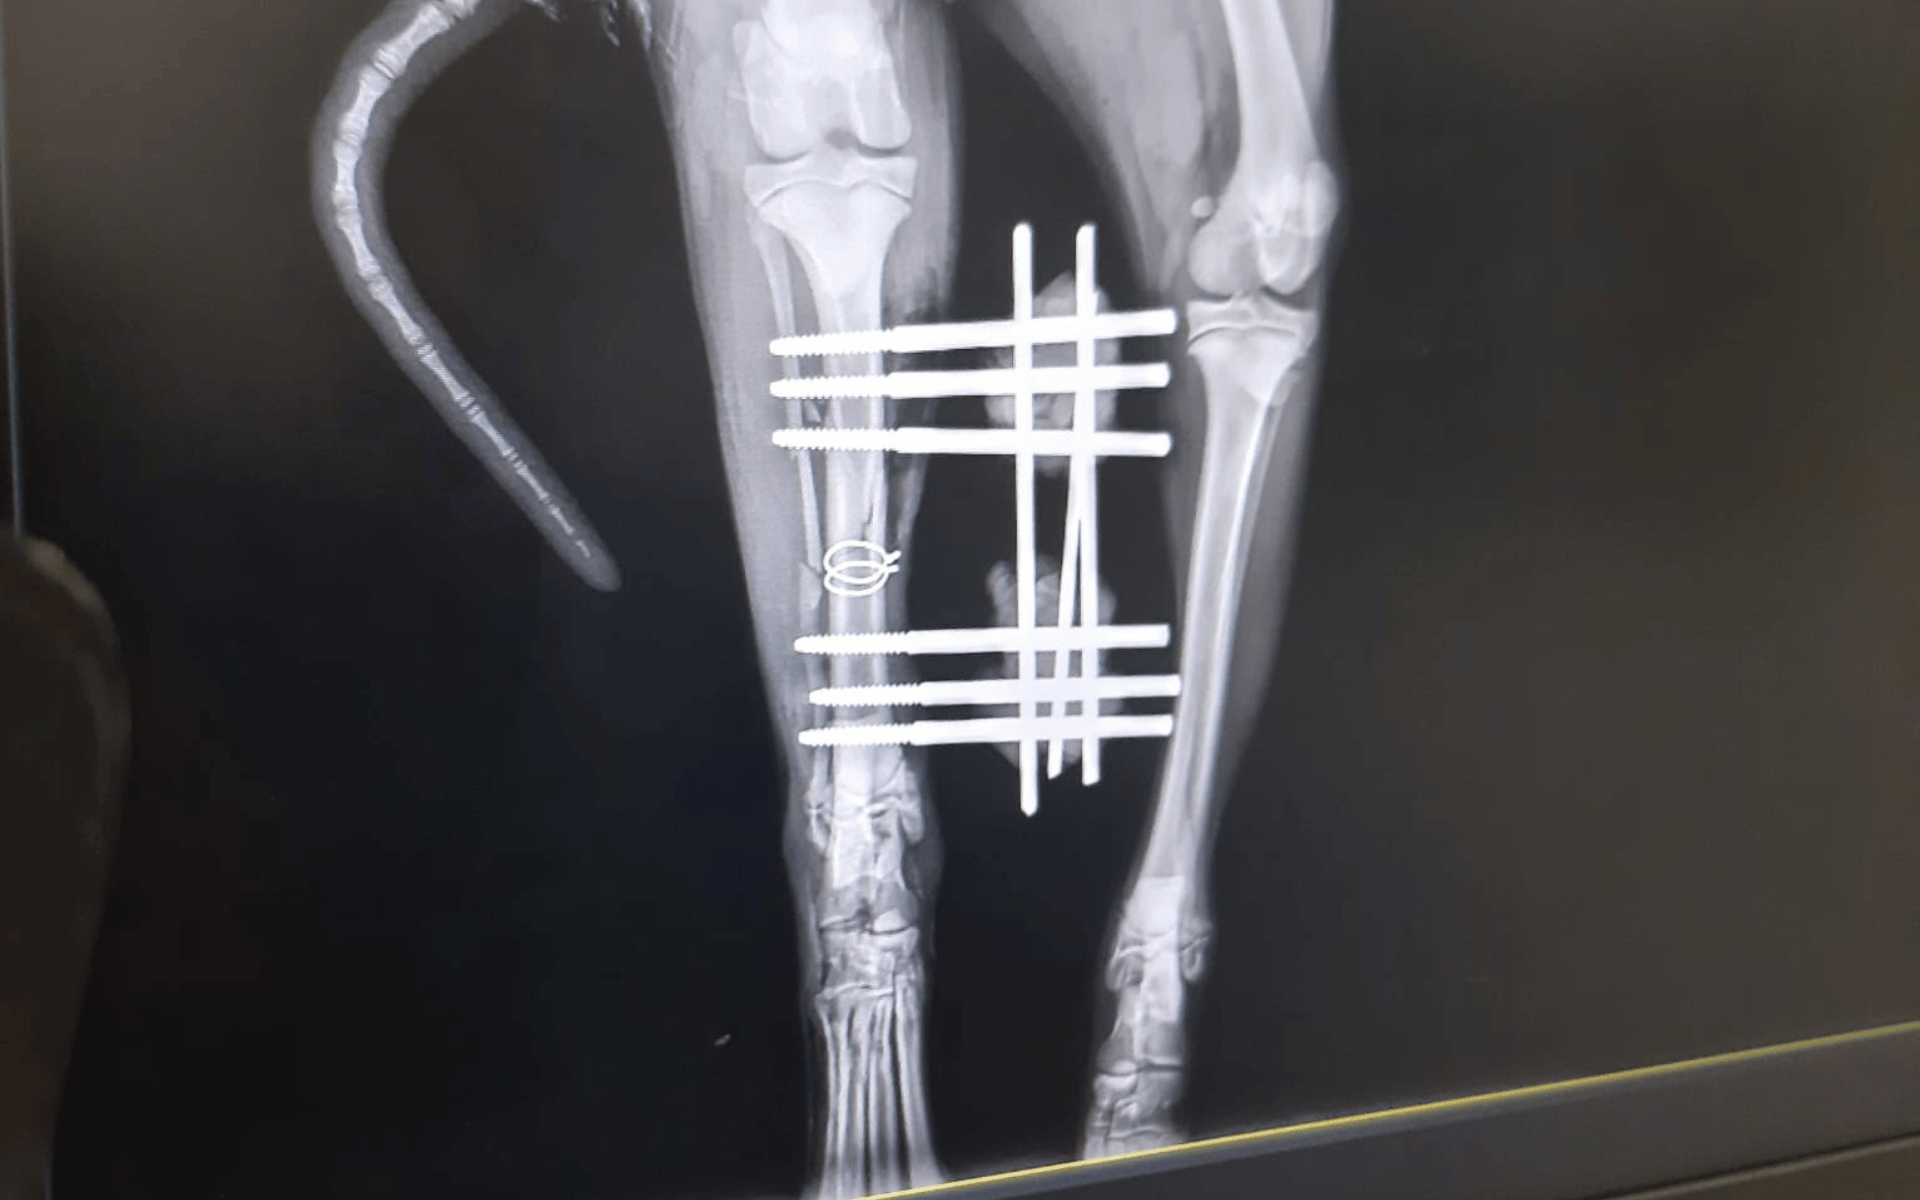

Bereits am nächsten Tag wurde Damian operiert. Um das Bein zu stabilisieren, musste ein Fixateur externe eingesetzt werden, den er nun mindestens zwei Monate tragen muss. Eine lange Zeit für einen jungen Hund – doch er zeigt sich tapfer und hat gute Chancen, wieder vollständig gesund zu werden.